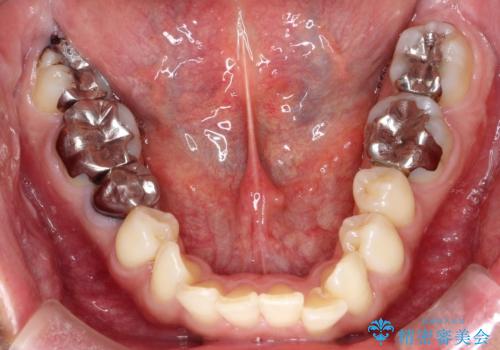

- 前歯の捻れを主訴に来院されました。

顔貌の正中と上顎前歯の正中があっており、下顎は顎位が偏位している状態でした。

今回は患者さんの希望もあり非抜歯にて歯列拡大、遠心移動を行なってできる限り前歯を下げながら配列する治療を行いました。